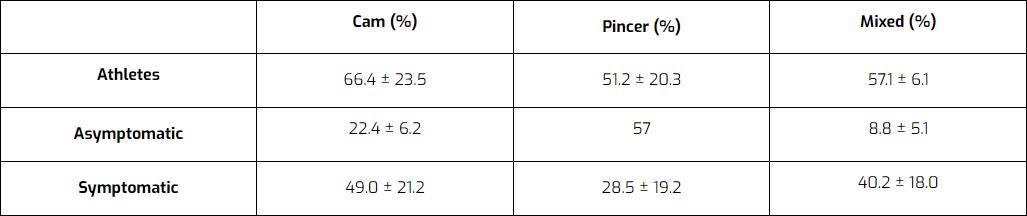

Si ipotizza che questa morfologia si sviluppi come adattamento specifico imposto dalle esigenze dell'adolescenza. È possibile che la placca di crescita si sposti, rendendo la testa meno rotonda, ma più grande. Una volta che le placche di crescita si chiudono, la morfologia non cambia più. La morfologia FAI è comune nelle persone asintomatiche e persino nel 50-70% degli atleti. Quindi molte persone presentano anomalie, ma solo una piccola parte sviluppa dolore.

Una revisione di Mascarenhas et al. (2016) elenca le percentuali di pazienti con FAI a camma, a tenaglia o a morfologia mista in popolazioni atletiche, asintomatiche e sintomatiche. I risultati: